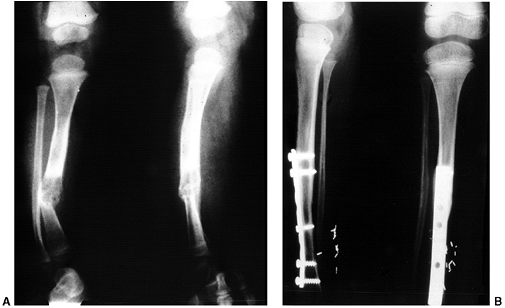

![]() |

|

Figure 28.5 A:

This 10-year-old girl is attempting to stand with her feet directly forward. The patellae face medially, and with effort she can direct the feet straight ahead. B: When the limb is positioned with the patella facing forward, the outward rotation of the foot becomes apparent. C: Examination in the prone position demonstrates approximately 80 degrees of internal rotation of the thigh, or medial femoral torsion. D: With knees flexed, the outward direction of the foot can also be appreciated. If the rotational deformities are complementary, foot progression may be deceptively normal. E: The combination of increased medial thigh rotation and external rotation of the lower leg segment may result in symptomatic torsional malalignment. This deformity may be a cause of nonspecific knee pain in adolescents because of the increased shear forces through the knee. F: Combined femoral external rotation and tibial internal rotation osteotomies correct the malicious malalignment. Knee symptoms are predictably improved. |